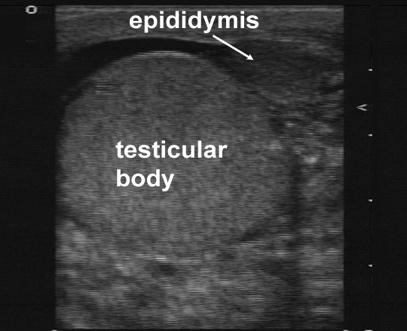

6. Then move to the “buddy view,” which is a transverse view of both testicles in the same image. Compare both testicles echogenicity, blood flow, and size. In a testicular torsion, you should see a decrease in echogenicity on the affected side (Figure 1), while in epididymitis you will generally see normal echogenicity and enlargement of the epididymis (Figure 2). Of note, echogenicity may be normal in intermittent or early torsion cases.

Figure 2. Enlarged Epididymis. Courtesy of Michael Blaivas, MD